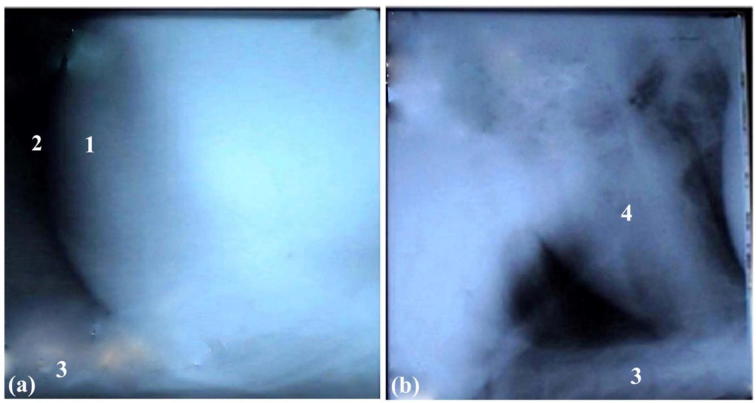

Fig. 2.

Lateral radiographic views of the cranial abdomen (a) and the thorax (b) of a 6-year-old non-pregnant female buffalo with traumatic reticuloperitonitis and pericarditis showing cardiomegaly with adhesions between heart and reticulum. Notice the heart lost its characteristic shape. 1: Nails; 2: Reticulum; 3: Sternum; 4: Adhesions; 5: Heart.

Fig. 3.

Lateral radiographic views of the cranial abdomen (a) and the thorax (b) of a 4-year-old non-pregnant female buffalo with traumatic pericarditis showing free reticulum, adhesions around the heart and unclear cardiac margins. 1: Heart; 2: Lungs; 3: Reticulum; 4: Sternum.

Fig. 4.

Lateral radiographic views of the cranial abdomen (a) and the thorax (b) of a 5-year-old pregnant female buffalo with traumatic reticuloperitonitis and pericarditis showing free reticulum and slight cardiac enlargement. 1: Reticulum; 2: Lungs; 3: Sternum; 4: Heart.